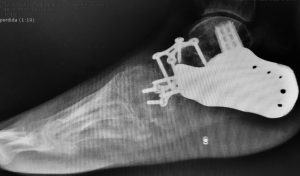

Prótesis de tobillo

Alternativa a la fusión (artrodesis) del tobillo. Mejora la calidad de vida de pacientes con artrosis severa permitiendo conservar cierto rango de movimiento.